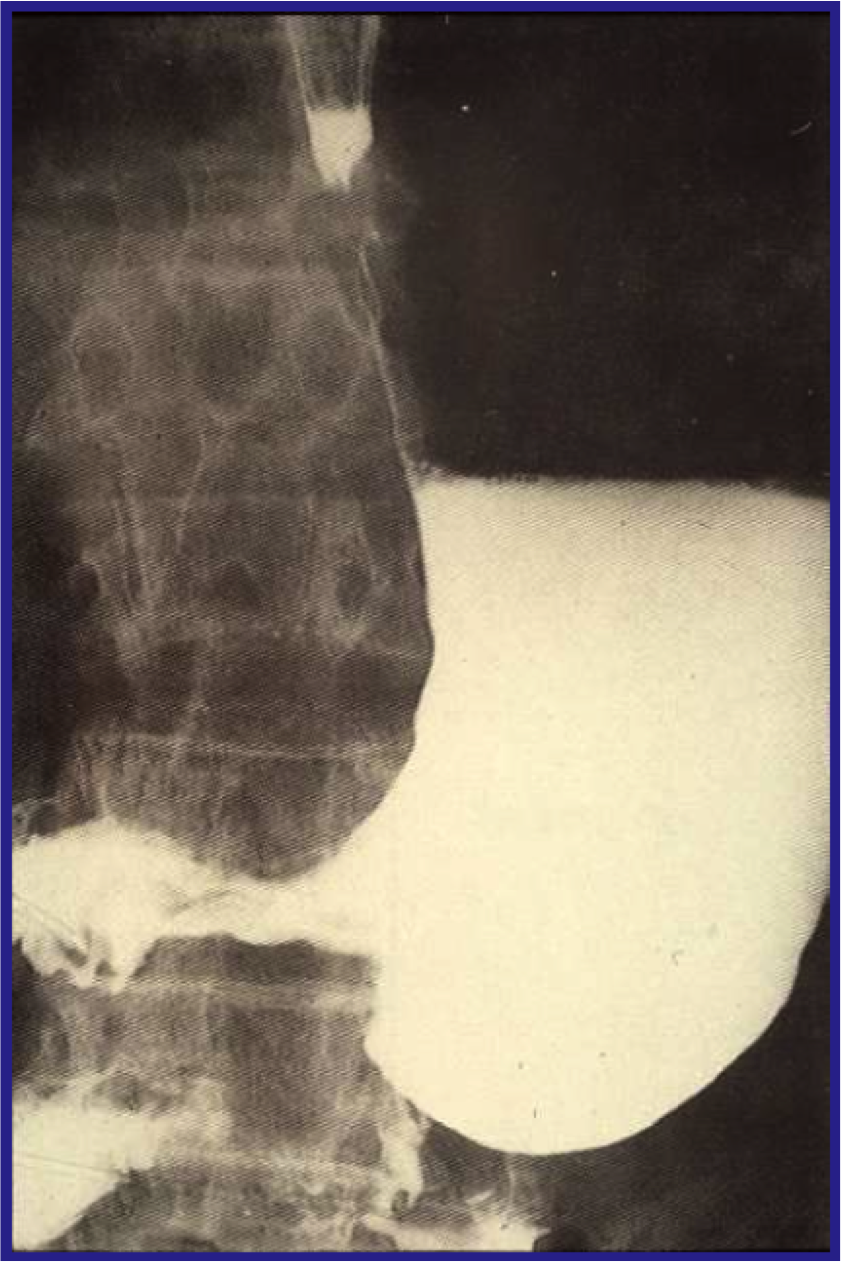

[*] The next most common malignancy is carcinoma of the oesophagus which may arise from the squamous or so-called columnar epithelial lined oesophagus. Dysphagia is common presenting symptom and many tumours are inoperable at the time of presentation.

[*] Oesophageal carcinoma Investigation:

[*] Oesophageal carcinoma pathological features